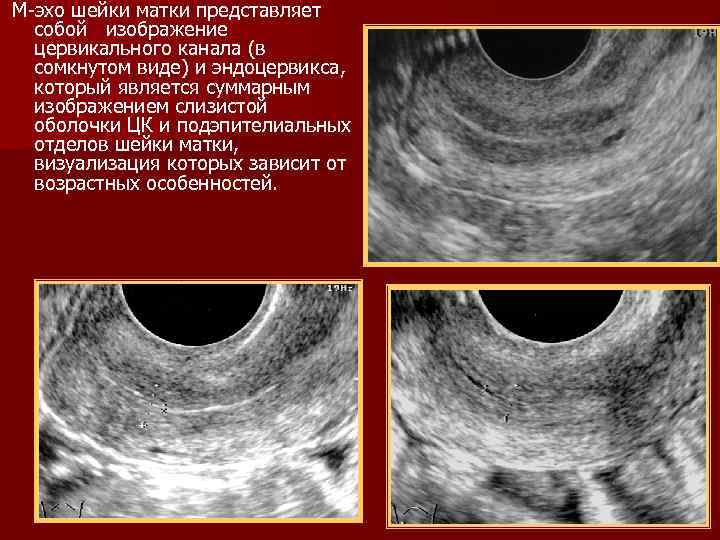

М-эхо шейки матки представляет собой изображение цервикального канала (в сомкнутом виде) и эндоцервикса, который является суммарным изображением слизистой оболочки ЦК и подэпителиальных отделов шейки матки, визуализация которых зависит от возрастных особенностей.

Репродуктивный возраст 15 -й день МЦ 18 -й день МЦ

Постменоапуза постменопауза более 5 лет постменопауза менее 5 лет